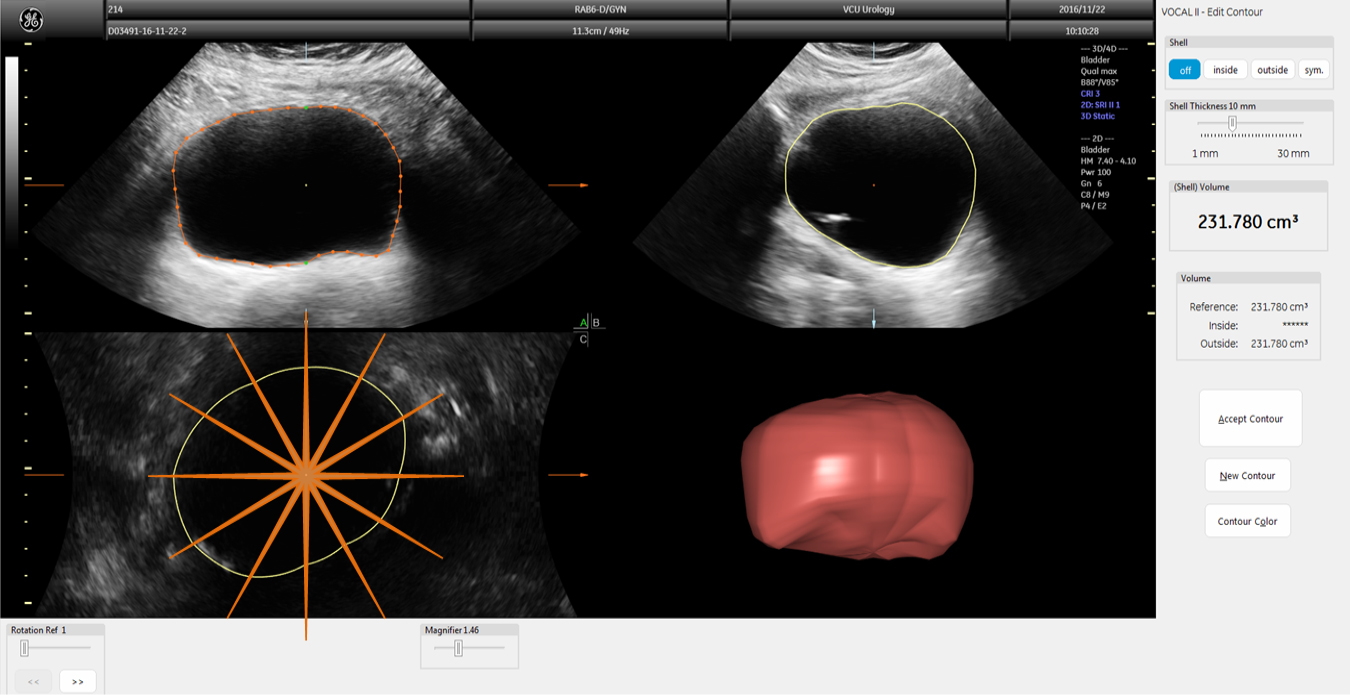

Methods: Twelve female participants with OAB completed an extended UD procedure with the addition of serial bladder ultrasound images captured once per minute. Bladder volume was measured using three ultrasound methods: (1) Vspheroid: two-dimensional (2D) method calculated assuming spheroid geometry; (2) Vbih: 2D correction method obtained by multiplying Vspheroid by a previously derived correction factor of 1.375; and (3) V3D: three-dimensional (3D) method obtained by manually tracing the bladder outline in six planes automatically reconstructed into a solid rendered volume. These volumes were compared to a control (Vcontrol) obtained by adding UD infused volume and the volume of estimated urine production.

Image calculations